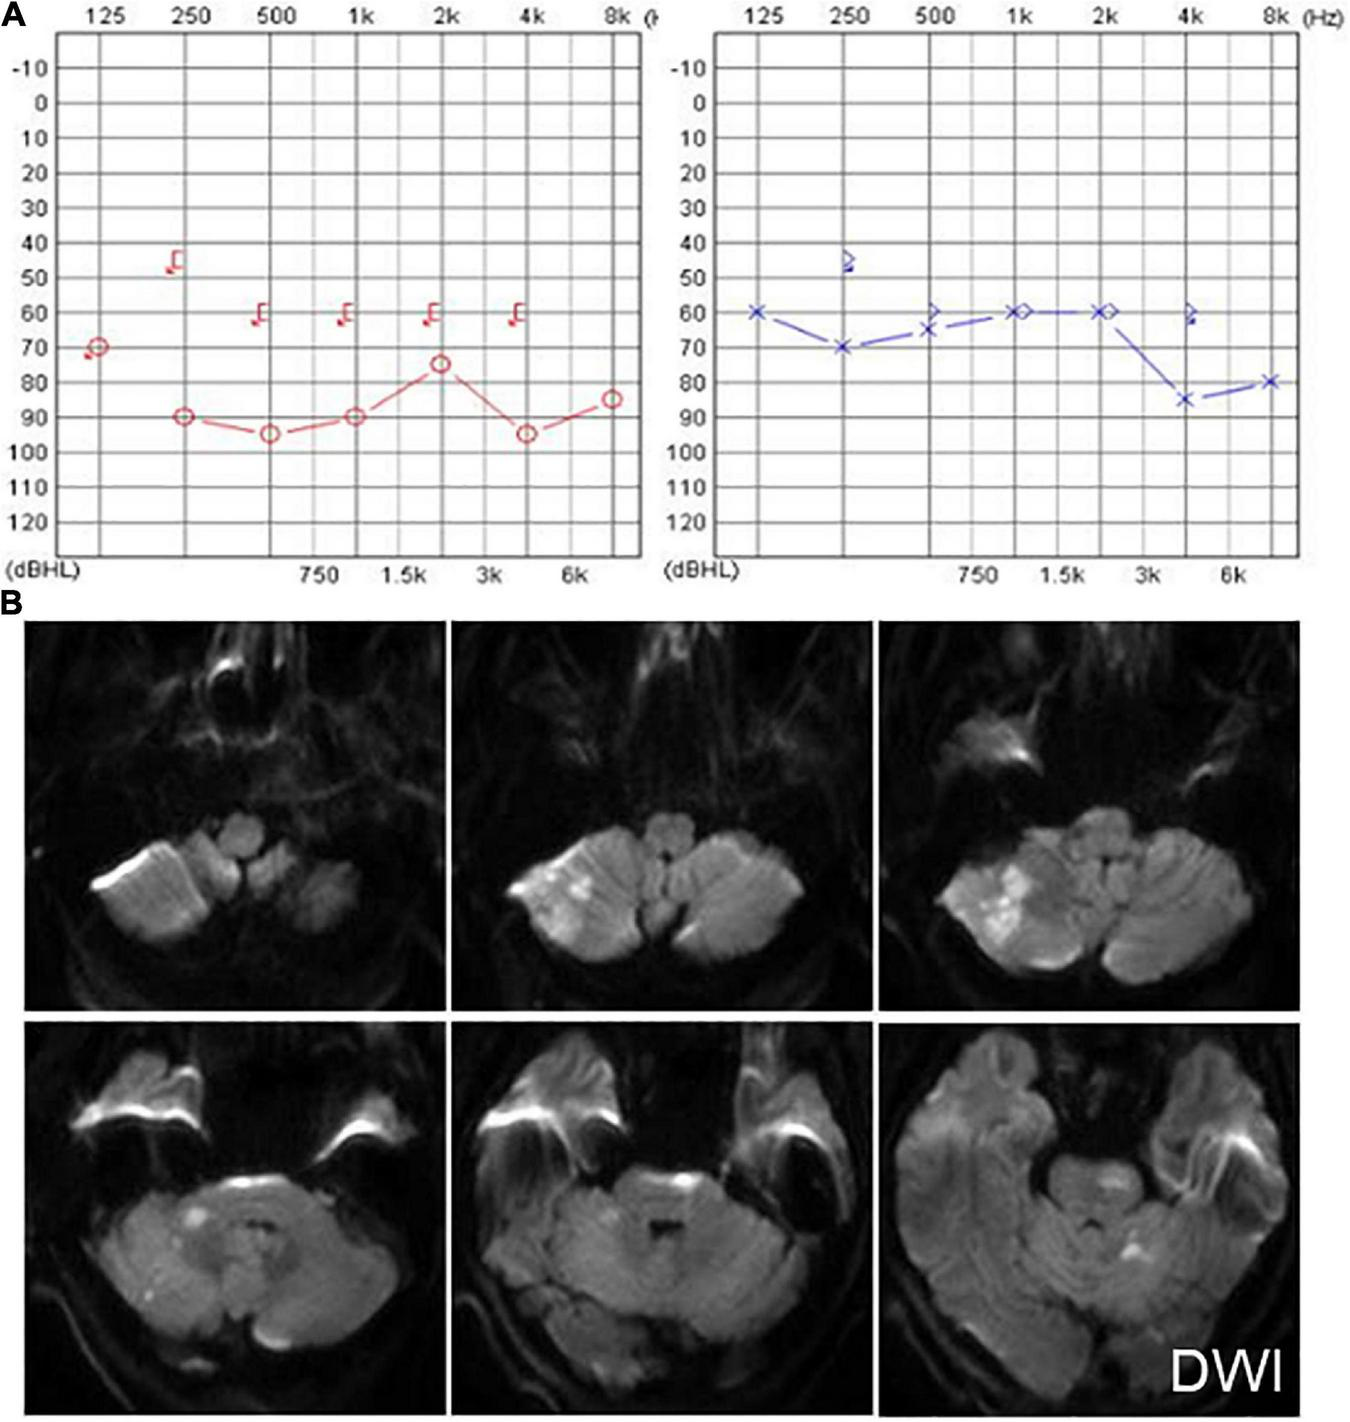

Six patients were diagnosed with posterior circulation infarction and/or ischemia, including 1 case of focal infarction of the medulla oblongata, 1 of infarction of the cochlear, and vestibular nuclei, 2 of cerebellar infarction, and 1 of extensive infarction of the brainstem and cerebellum. One patient with a focal infarction of the medulla oblongata had SN (III°), obvious oculomotor abnormalities (including gaze-evoked nystagmus; Supplementary Video 2), and abnormal saccade and pursuit. The vHIT results showed reduced VOR gains of three semicircular canals on the right side, and magnetic resonance angiography (MRA) revealed vertebrobasilar artery stenosis (Figure 3A). MRI revealed acute infarction of the right medulla oblongata, which involved the ipsilateral vestibular nucleus (Figures 3B,C). The patient with infarction of the cochlear and vestibular nuclei presented with persistent dizziness, right facial discomfort, and decreased muscle strength in the right limbs. Backward tilting was seen during the Romberg test and the Fukuda test was unstable. PTA indicated total deafness on the right side (Figure 4A). MRI showed that the infarcted focus of the right medulla oblongata near the pons involved the cochlear nucleus and vestibular nucleus (Figure 4B).

Another patient presented with continuous dizziness and sudden bilateral hearing loss; MRI revealed extensive infarction of the brainstem and cerebellum. PTA showed bilateral sensorineural hearing loss (Figure 5A), and brain MRI revealed lacunar foci in the bilateral basal ganglia (Figure 5B). The symptoms of both patients with cerebral infarction included vertigo with nausea and vomiting for 1 day, accompanied by DBN (Supplementary Video 3A). Brain MRI revealed bilateral basal ganglia and paraventricular infarcts. The other two patients had brainstem and basal ganglia ischemia and presented with DBN (Supplementary Video 3B).